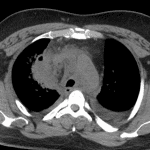

CT

- Chest

- Area of masslike consolidation in the paramediastinal right upper lobe with internal locules of gas

- Extensive contiguous mediastinal fat stranding extending from the thoracic inlet through the infrahilar region without mediastinal gas or defined mediastinal collection

- Large pericardial effusion, measuring 2 cm in width

- Multiple mildly enlarged mediastinal and bilateral hilar lymph nodes, likely reactive

- Calcified mediastinal and right hilar lymph nodes

- Tree-in-bud and groundglass opacities scattered throughout the right lung with interlobular septal thickening

- Moderate-sized bilateral pleural effusions

- Mediastinitis

- Pulmonary abscess

Findings concerning for a right upper lobe pulmonary abscess with adjacent mediastinitis. No mediastinal gas or drainable mediastinal fluid collection. Recommend followup imaging after treatment to ensure resolution.

Groundglass opacities and tree-in-bud nodularity throughout the right lung likely relate to atypical infection.

Large pericardial effusion, likely representing reactive pericarditis. Recommend correlation with clinical findings of cardiac tamponade.